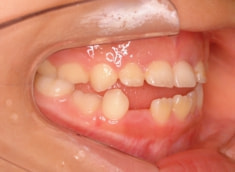

治療前

治療後(1年5ヶ月後)